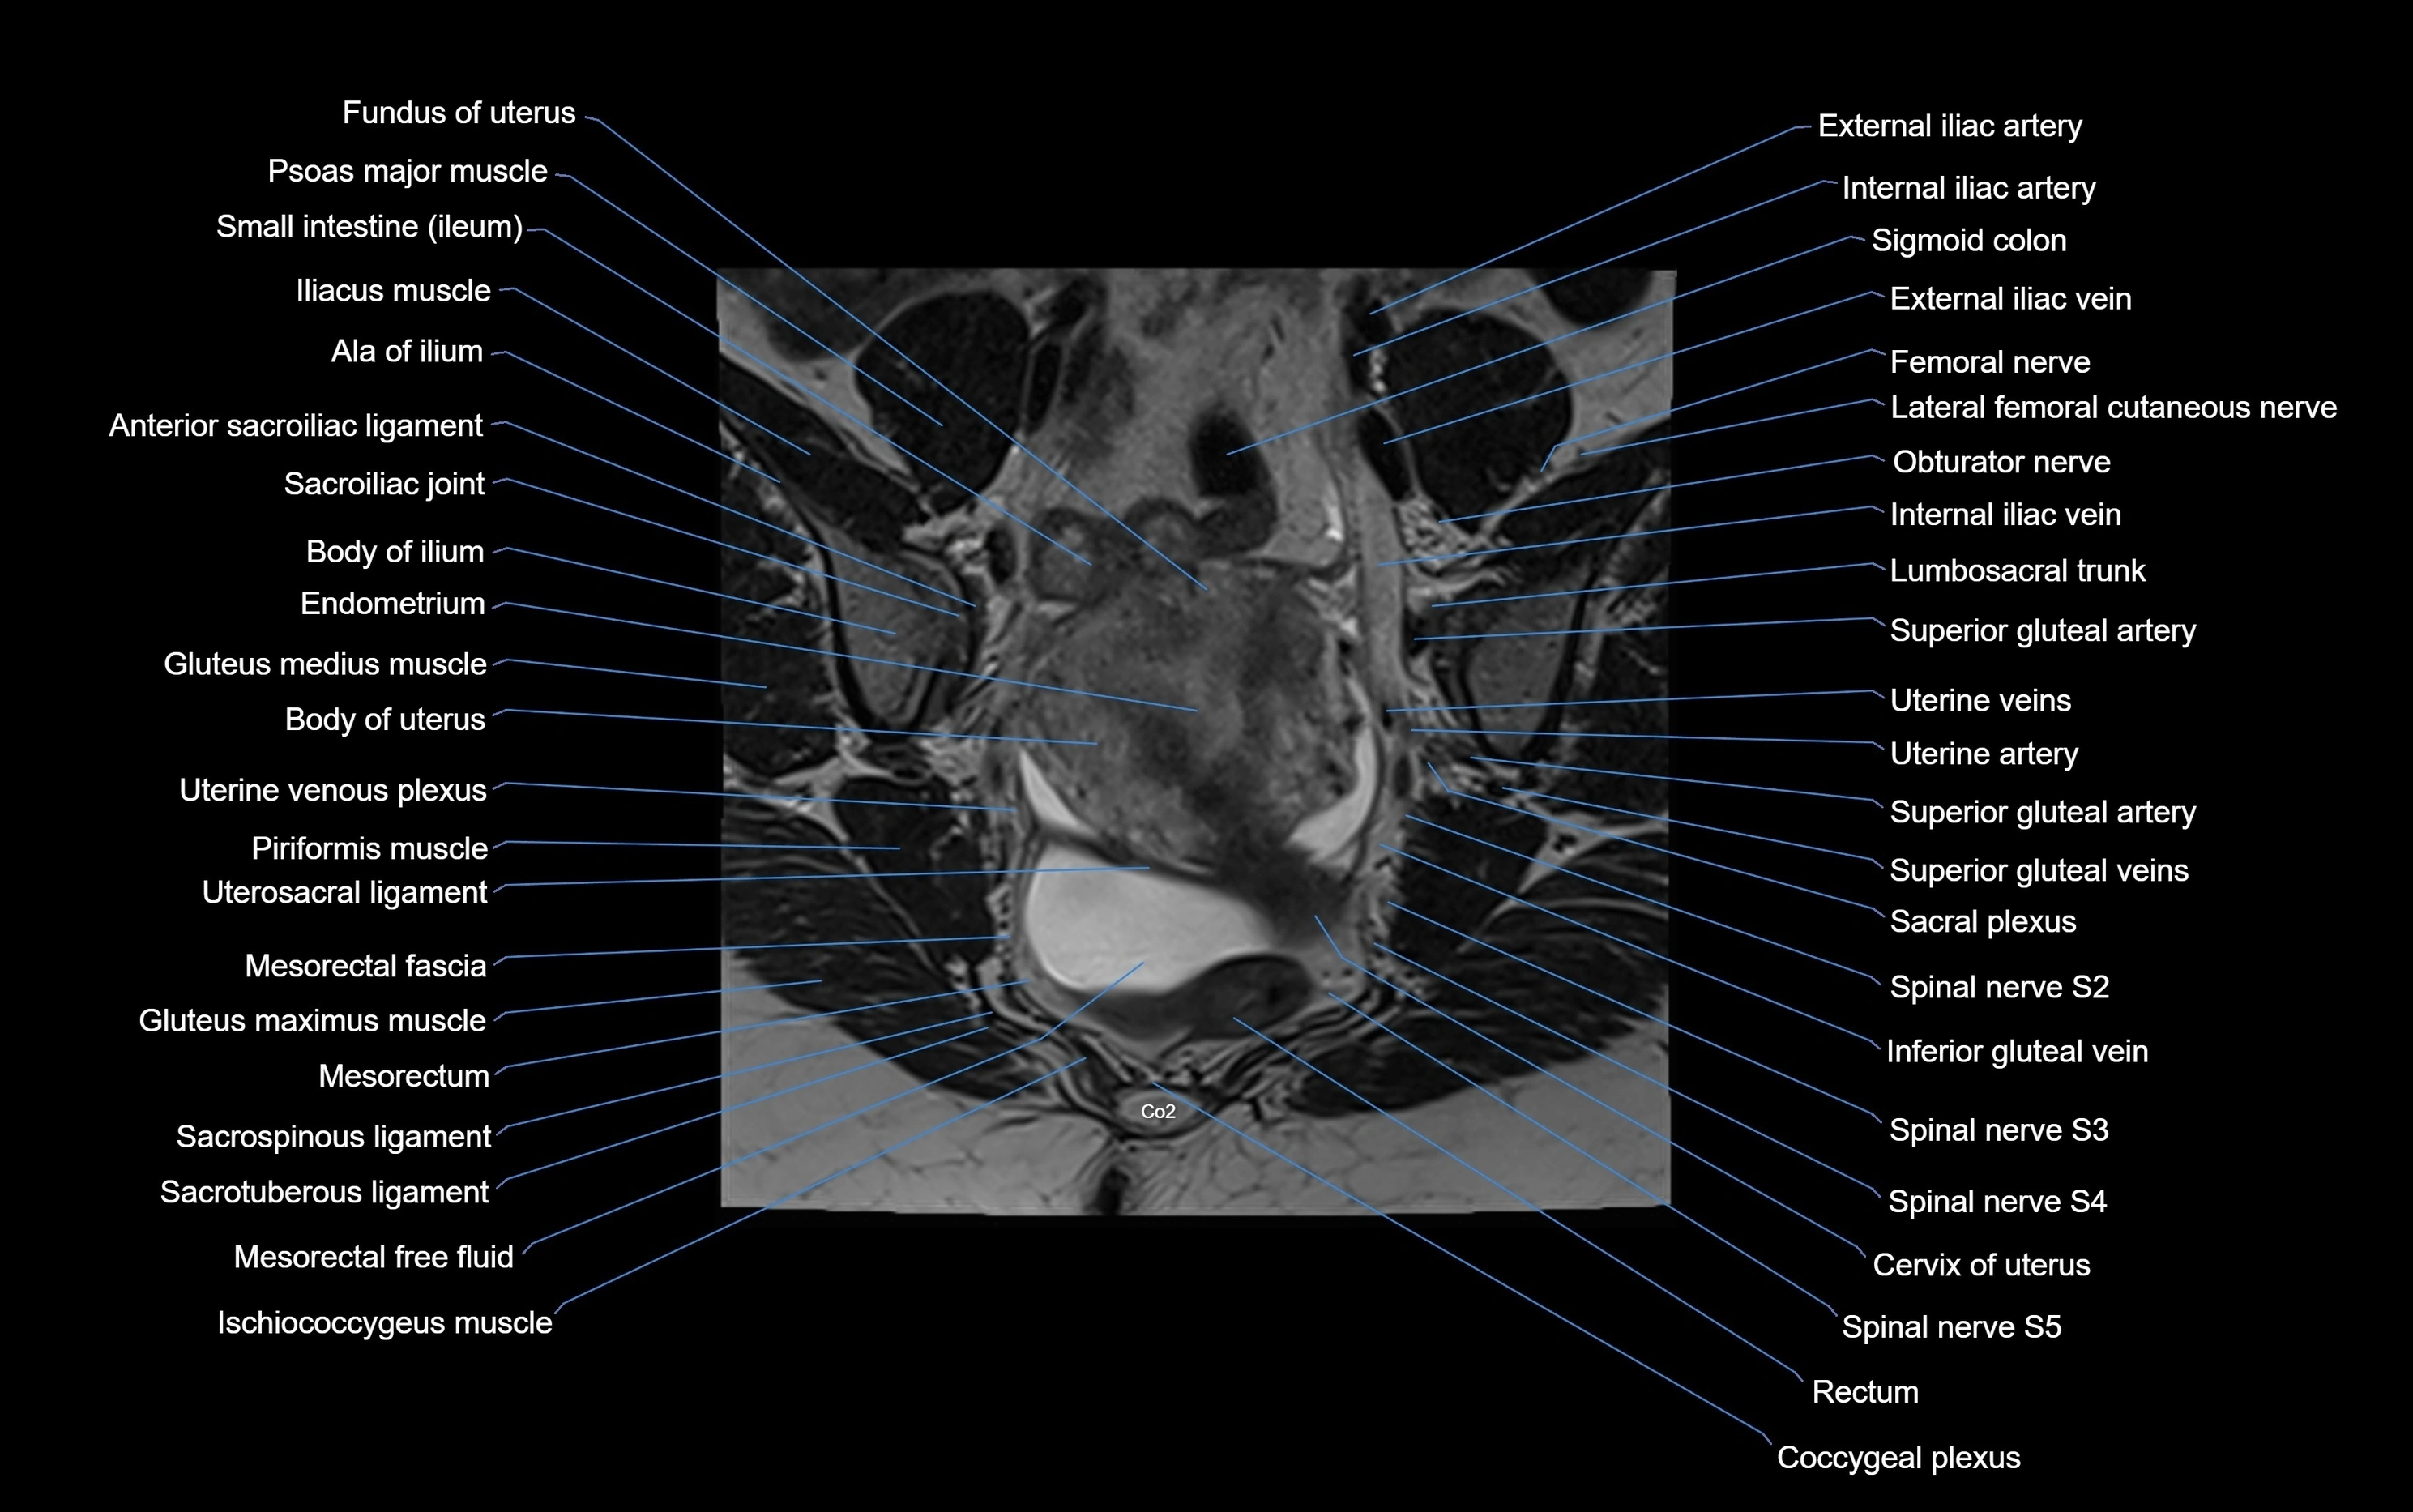

MRI image

image